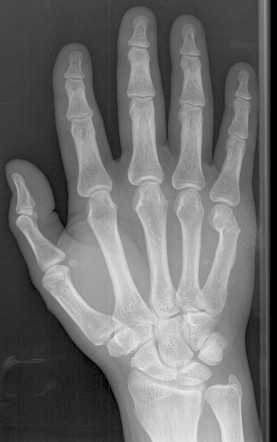

Most common metacarpal fracture? Most common anatomic location?

5th MC Neck of MC

Boxer’s fracture?

Base of 5th MC